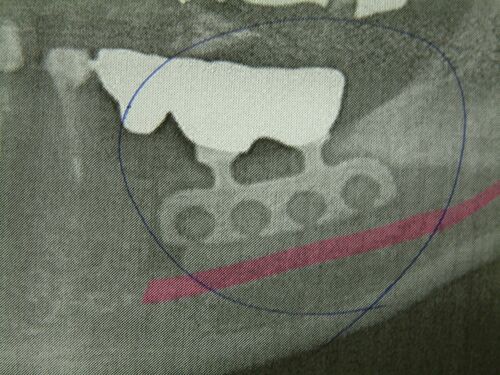

インプラントって一生ものじゃなかったの? 2

こんにちは。 手術後1週間は顎が腫れ、傷口から染み出る出血を殺菌うがい薬で日に何回となく口をすすぐ。 痛み止めを飲みながら1週間を悶々と過ごした。食事もろくに喉を通らない。片方の奥歯ではまともに噛めないからだ。 当時、僕はすでにサラリーマンを…